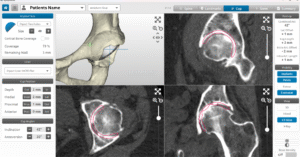

If total hip replacement is considered the most appropriate treatment, Dr Hockings will organise further diagnostic imaging to assist with surgical planning. You’ll be referred for a CT scan, which is used to create a 3D model of your hip using MyHip software for precise, patient-specific planning. Additional tests such as X-rays, blood tests, and general health checks may also be arranged as needed.

Once your CT scan has been completed, Dr Jason Hockings will use the data to develop a personalised 3D surgical plan using MyHip digital planning software. This system allows him to visualise your hip joint in three dimensions and assess your bone shape, joint orientation, and surrounding anatomy with precision.

Using this model, Dr Hockings can plan the size, position, and alignment of each implant component before surgery. This planning helps guide leg length, joint stability, and muscle balance while minimising the need for adjustments during the procedure.

Preparing the hip socket: The acetabulum is reshaped and smoothed to create a stable foundation for the new socket component. The MyHip plan helps guide the position, angle, and depth of preparation so the implant sits securely and functions smoothly.